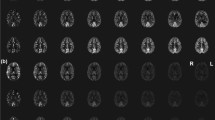

Image acquisition was performed successfully in all volunteers, and no data sets had to be discarded due to movement or misplaced labelling foci. Figure 2 shows representative images of both quantitative CBF images of all flow territories (a) and relative CBF images of the RICA and a difference image of both (b). The difference image was created by subtracting the conventional image from the self-controlled ss-ASL. This image shows the difference in signal in the peripheral grey matter zones that is mostly image noise, indicating no major differences between the two methods (red arrows).

(a) Representative images of one volunteer after quantification of CBF data. In the upper row, non-selective and conventional super-selective ASL images are presented. The bottom row shows self-controlled super-selective ASL images. Both the selectivity and the quantitative values appear similar in all approaches (b) Relative CBF (rCBF) images of the RICA showing the gain in SNR of self-controlled ss-ASL compared to the conventional approach, and a difference image of both approaches. The difference image shows differences in signal, which can be largely attributed to noise, indicating no significant differences between methods (red arrows)

Quantitative CBF measures were similar for conventional ASL, super-selective ASL and self-controlled ASL imaging. The results for each individual volunteer are listed in Table 1. The CBF values for all three methods differed by less than ± 5 ml/min/100 g for each artery. No major deviations were found in either of the carotid arteries, and the Pearson correlation coefficients appeared similar (r = 0.97 – 0.98).

Regarding the posterior circulation, both selective approaches displayed lower correlation compared to non-selective ASL (r = 0.87 for both), while the comparison between selective approaches showed a high correlation (r = 0.99).

Figure 3 shows the linear regression curves of the results alongside the Pearson correlation coefficient (r).

ANOVA testing showed an F-value of 0.076 for the RICA, 0.002 for the LICA and 0.131 for the BA, with the critical F-value at 3.682 for all tests.